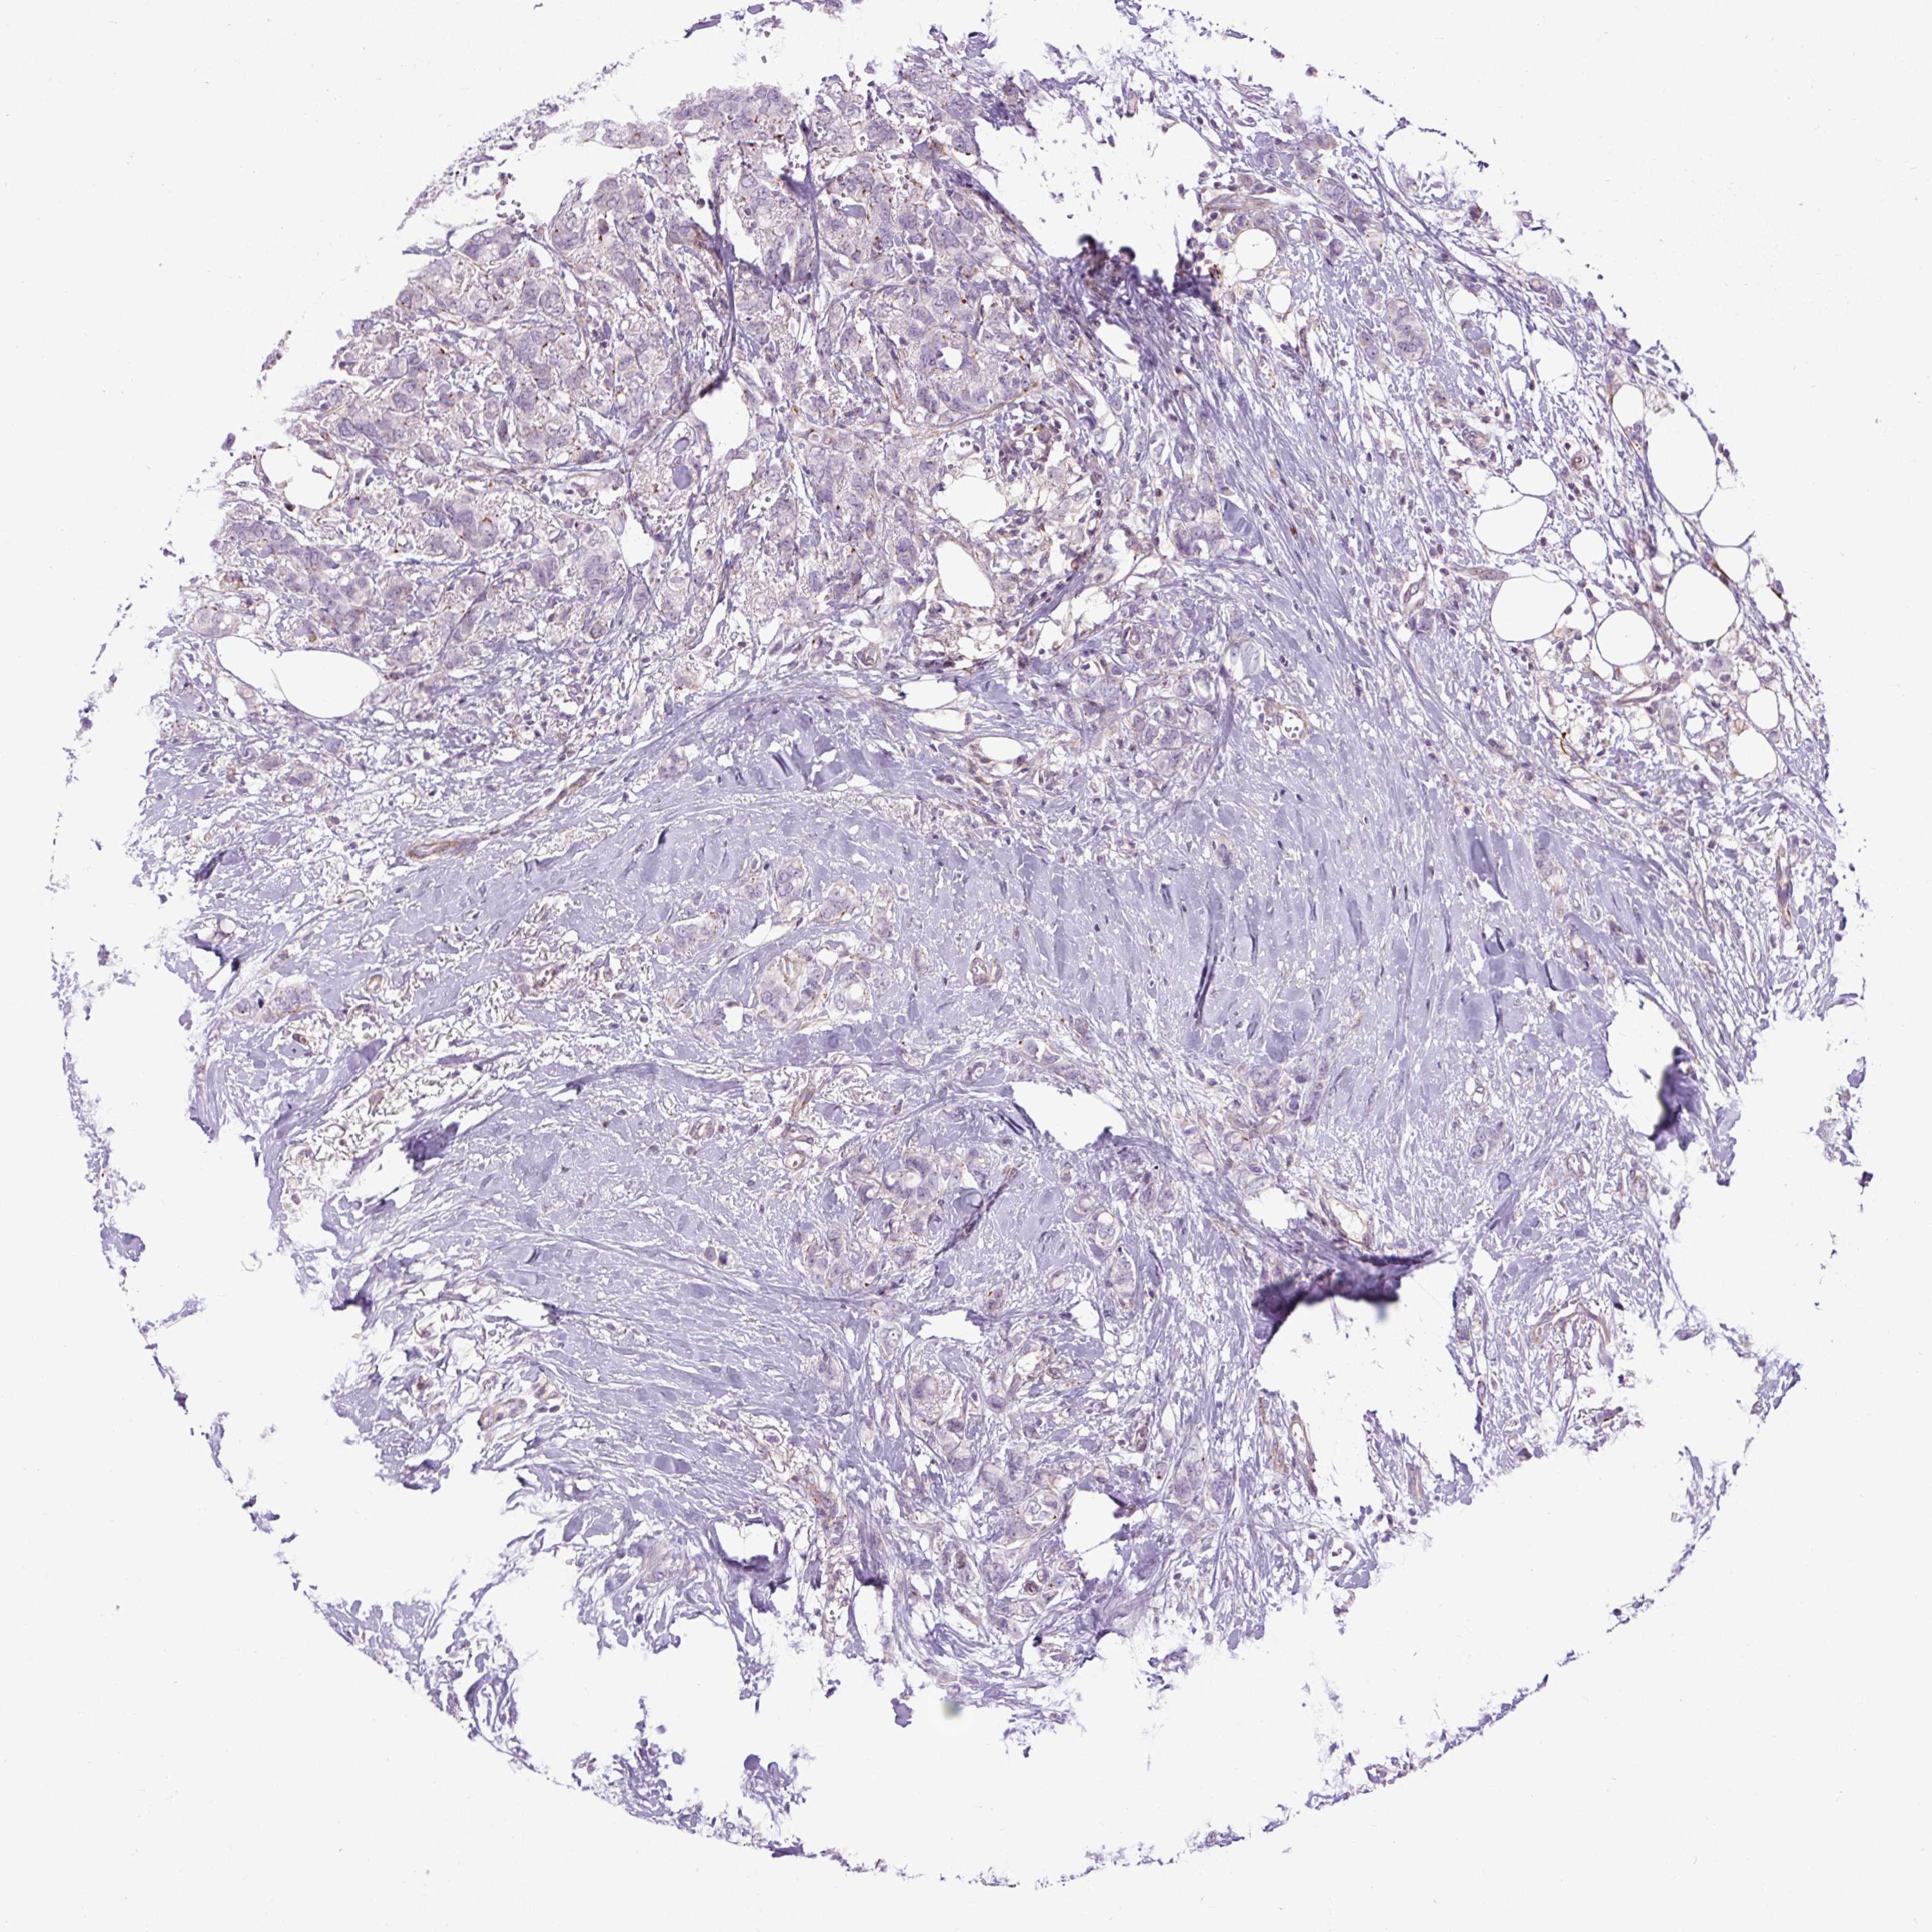

CANCER BREAST CANCER Show tissue menu

Breast cancer

Human cancer